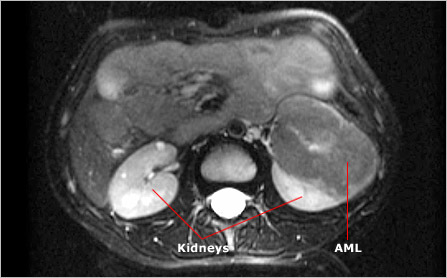

Angiomyolipomas (AMLs) occur in 70 to 80 percent of adults with TSC. These generally benign tumors may occur in children as young as two years old, but most often arise after age five. The name of these tumors refers to their composition: an abnormal collection of blood vessels (angio), smooth muscle (myo), and fat (lipoma). Most people with TSC develop multiple AMLs in both kidneys. In cases where AMLs remain relatively small (less than 4 cm in diameter), they generally cause few problems. Large tumors, however, can negatively affect kidney function by crowding and destroying healthy organ tissue. They can also cause internal hemorrhages if blood vessels associated with them rupture. Such internal bleeding can cause pain and, in rare cases, be life threatening if it goes untreated.

Although single AMLs occur in people who don't have TSC, multiple AMLs are considered characteristic of the disorder and are a major feature in the diagnostic criteria for TSC. Most AMLs are benign. However, people with TSC are more likely than those without the disorder to develop malignant kidney tumors. The rate of malignancy among people with TSC is 1 to 2 percent.